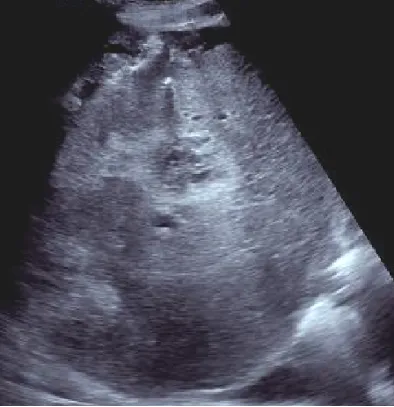

● 巨块型肝癌:体积较大,>5cm

高回声多见,多伴有液化坏死

无纤维包膜(浸润性生长)

易并发肝破裂出血

● 结节型:肿瘤直径多在3~5cm,单发或多发

不均匀高回声或低回声为主,与周围肝组织分界较清,外周常有低回声的声晕

常合并肝硬化或慢性肝病史

● 弥漫型:弥漫散布于整个肝脏,直径在1.0cm左右,肝脏形态失常。

以不均匀低回声多见浸润生长,边界不清,外周一般无声晕或包膜回声。

常伴有肝硬化,与再生结节较难鉴别。